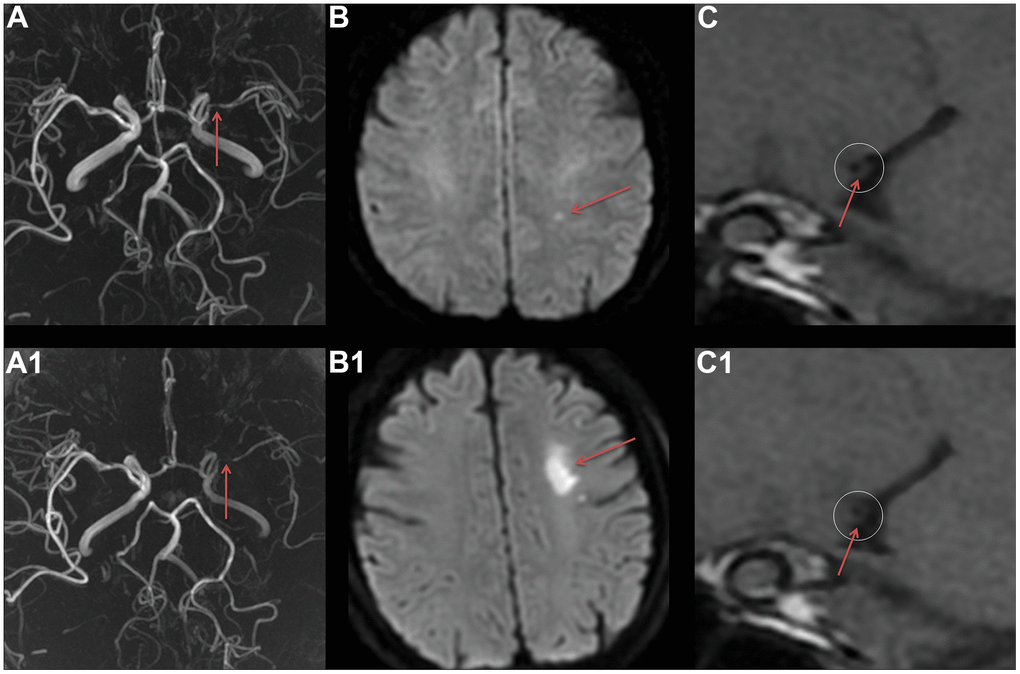

Figure 1. The VWMRI of MCA plaque characteristic in a patient with ischemic stroke recurrence. A female patient, 56 years old, experienced her first ischemic stroke in August 2019. MRA revealed severe stenosis of the M1 segment of the left MCA (A). At the same time, DWI displayed a punctate high signal in the left centrum semiovale (B), and VWMRI revealed centripetal thickening of the MCA and severe lumen stenosis (C). In November 2019, the patient experienced a recurrent ischemic stroke. MRA displayed an aggravated stenosis of the M1 segment of the left MCA (A1), and DWI showed a new patchy high signal in the left centrum semiovale (B1). Furthermore, VWMRI revealed an aggravated centripetal thickening of the MCA and a worsening lumen stenosis (C1).